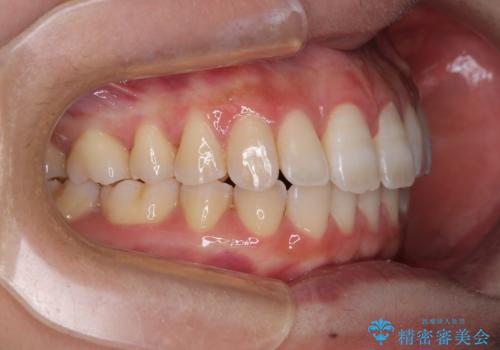

下顎前歯が2歯欠損しており、スペースになっており、上顎は叢生歯列となってしました。

奥歯の咬み合わせを考えると、理想的には2歯、最低でも1歯は下顎前歯の欠損部にインプラントやブリッジにより歯数を増やす必要がありました。

周囲の歯を削らないようにするためインプラントがおすすめとなりますが、歯根の移動が不十分な場合にはインプラントを埋入する幅が獲得できないため、その場合にはオールセラミックブリッジにより補綴治療を行うこととして、矯正治療を行うこととしました。

当初は上記計画でしたが、レントゲン撮影よりインプラント埋入は困難と判断され、患者様と相談の上、歯を削ってブリッジとするよりも、奥歯の咬み合わせを多少妥協することとなっても、スペースを閉じて仕上げていくこととしました。